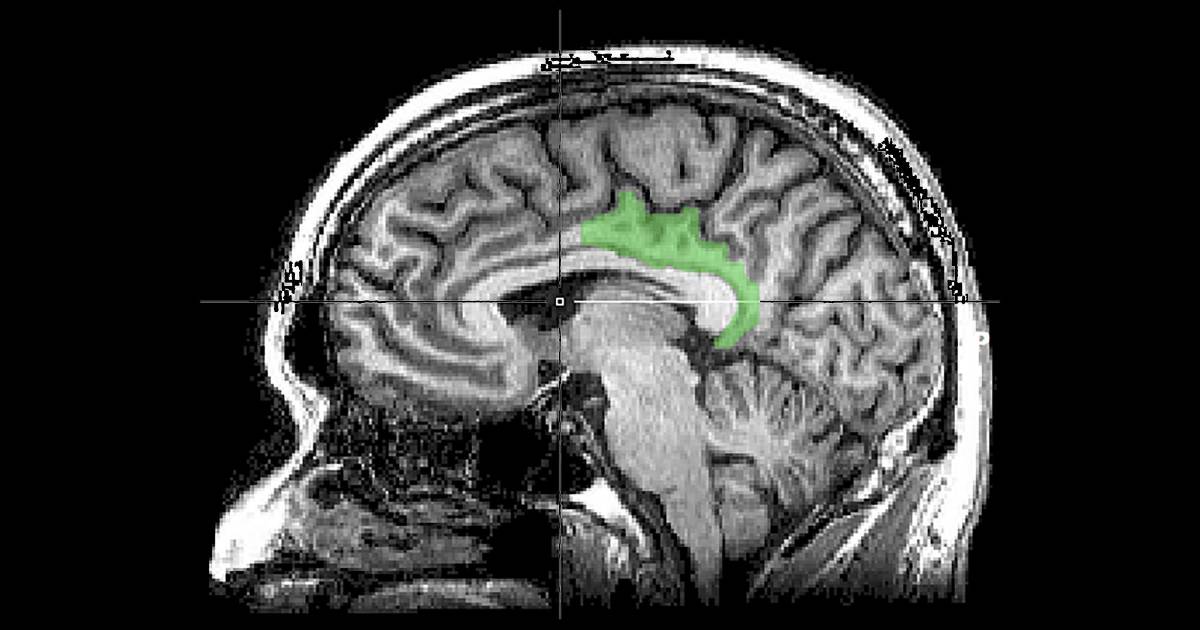

Al parecer, los recuerdos traumáticos activaron una zona distinta del cerebro: el giro cingulado posterior (GCP), el cual suele estar involucrado en el pensamiento dirigido internamente, como la introspección o la ensoñación. Mientras más graves eran los síntomas de TEPT de la persona, mayor actividad aparecía en el GCP.

Lo sorprendente de este hallazgo es que el GCP no se conoce como una región de la memoria, sino que está involucrado con el “procesamiento de la experiencia interna”, mencionó Schiller.

Ruth Lanius, directora de investigación sobre el TEPT en la Universidad de Ontario Occidental, quien no estuvo involucrada en el estudio, describió esos hallazgos como “trascendentales”, tanto porque establecen que los recuerdos traumáticos tienen vías distintas como porque indican que los mecanismos clave de un recuerdo traumático pueden estar involucrados con zonas del cerebro menos estudiadas. Gran parte de la investigación sobre el TEPT se ha centrado en la amígdala, el centro de detección del estrés en el cerebro, y el hipocampo, explicó Lanius. El giro cingulado posterior está “muy involucrado en la evocación de recuerdos” y en la búsqueda de la autorrelevancia, lo cual podría explicar por qué un recuerdo sensorial puede provocar miedo o pánico abrumadores.